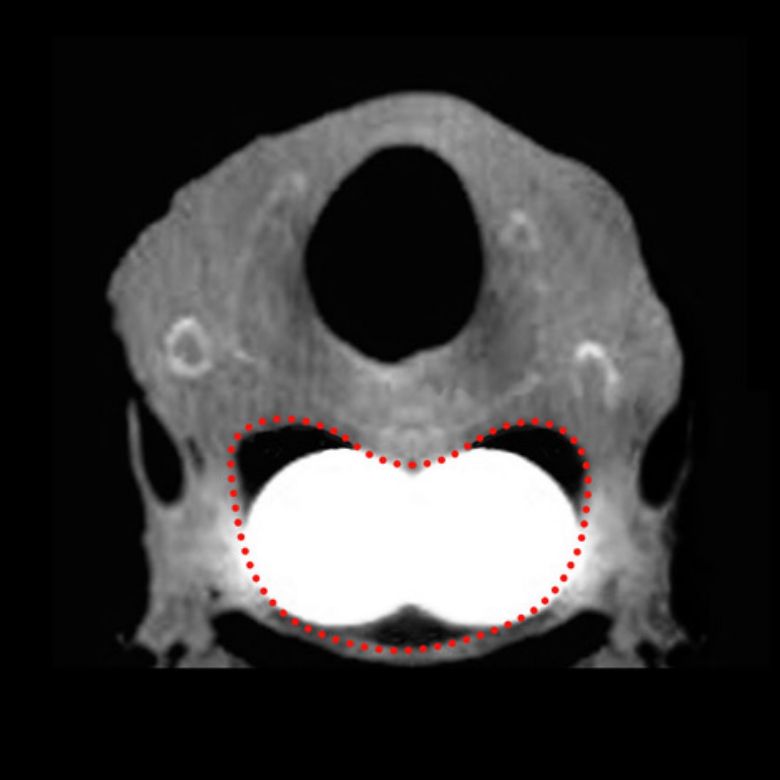

Contemporary research has confirmed that the upper esophageal sphincter is not round. Conventional devices address less than half of the mean cross section of the upper esophageal sphincter1,2.

Contoured to the physiology of the Upper Esophageal Sphincter

Infinity™ is contoured to the specific physiology of the upper esophageal sphincter, providing nearly double the lateral inflation dimension of conventional devices. Available exclusively from Bryan Medical.

The Infinity™ Esophageal Dilation System provides nearly double the lateral inflation dimension of conventional devices.